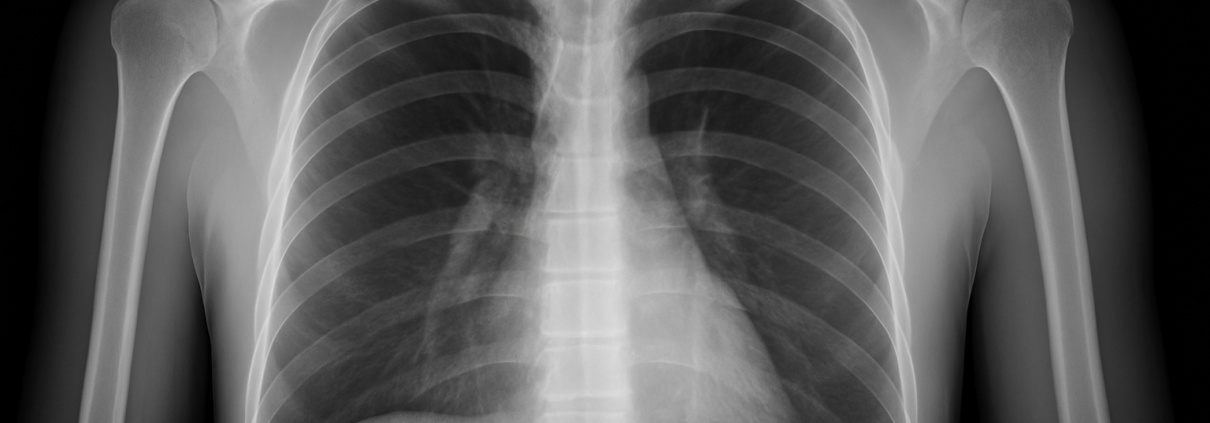

Contrairement à une photo classique, les examens d’imagerie ne capturent pas une image au sens visuel : ils traduisent des signaux physiques en images interprétables par le radiologue. La radiographie utilise les rayons X pour repérer les tissus denses comme les os. Le scanner, ou tomodensitométrie, superpose plusieurs coupes radiographiques pour obtenir une vision en 3D.

Une image à lire, pas à voir

Les images produites ne sont pas toujours évidentes à lire pour un non-initié. Ce que l’on voit, c’est une traduction codée de différences de densité, de signal ou d’écho. Les tissus se dessinent en nuances de gris ou en contrastes, mais leur interprétation dépend du contexte : un même aspect peut être normal ou pathologique selon l’âge, les antécédents, les symptômes. Le rôle du radiologue est donc central : il ne se contente pas de regarder, il analyse, compare, réconcilie l’image avec le patient. L’“image invisible” est celle de l’interprétation : c’est elle qui donne sens aux pixels. Les outils deviennent de plus en plus précis, avec des logiciels d’amplification, d’intelligence artificielle, de reconstruction 3D. Mais la lecture humaine reste irremplaçable pour contextualiser.